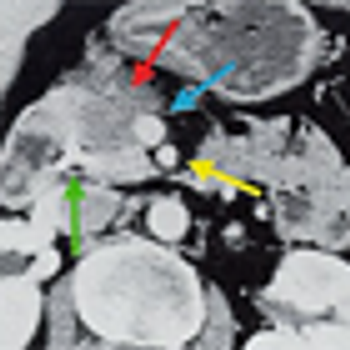

This slide show features a CT image, and pathology images of gastrointestinal stromal tumors (GISTs) arising in the stomach using H&E, CD34, and c-Kit staining.